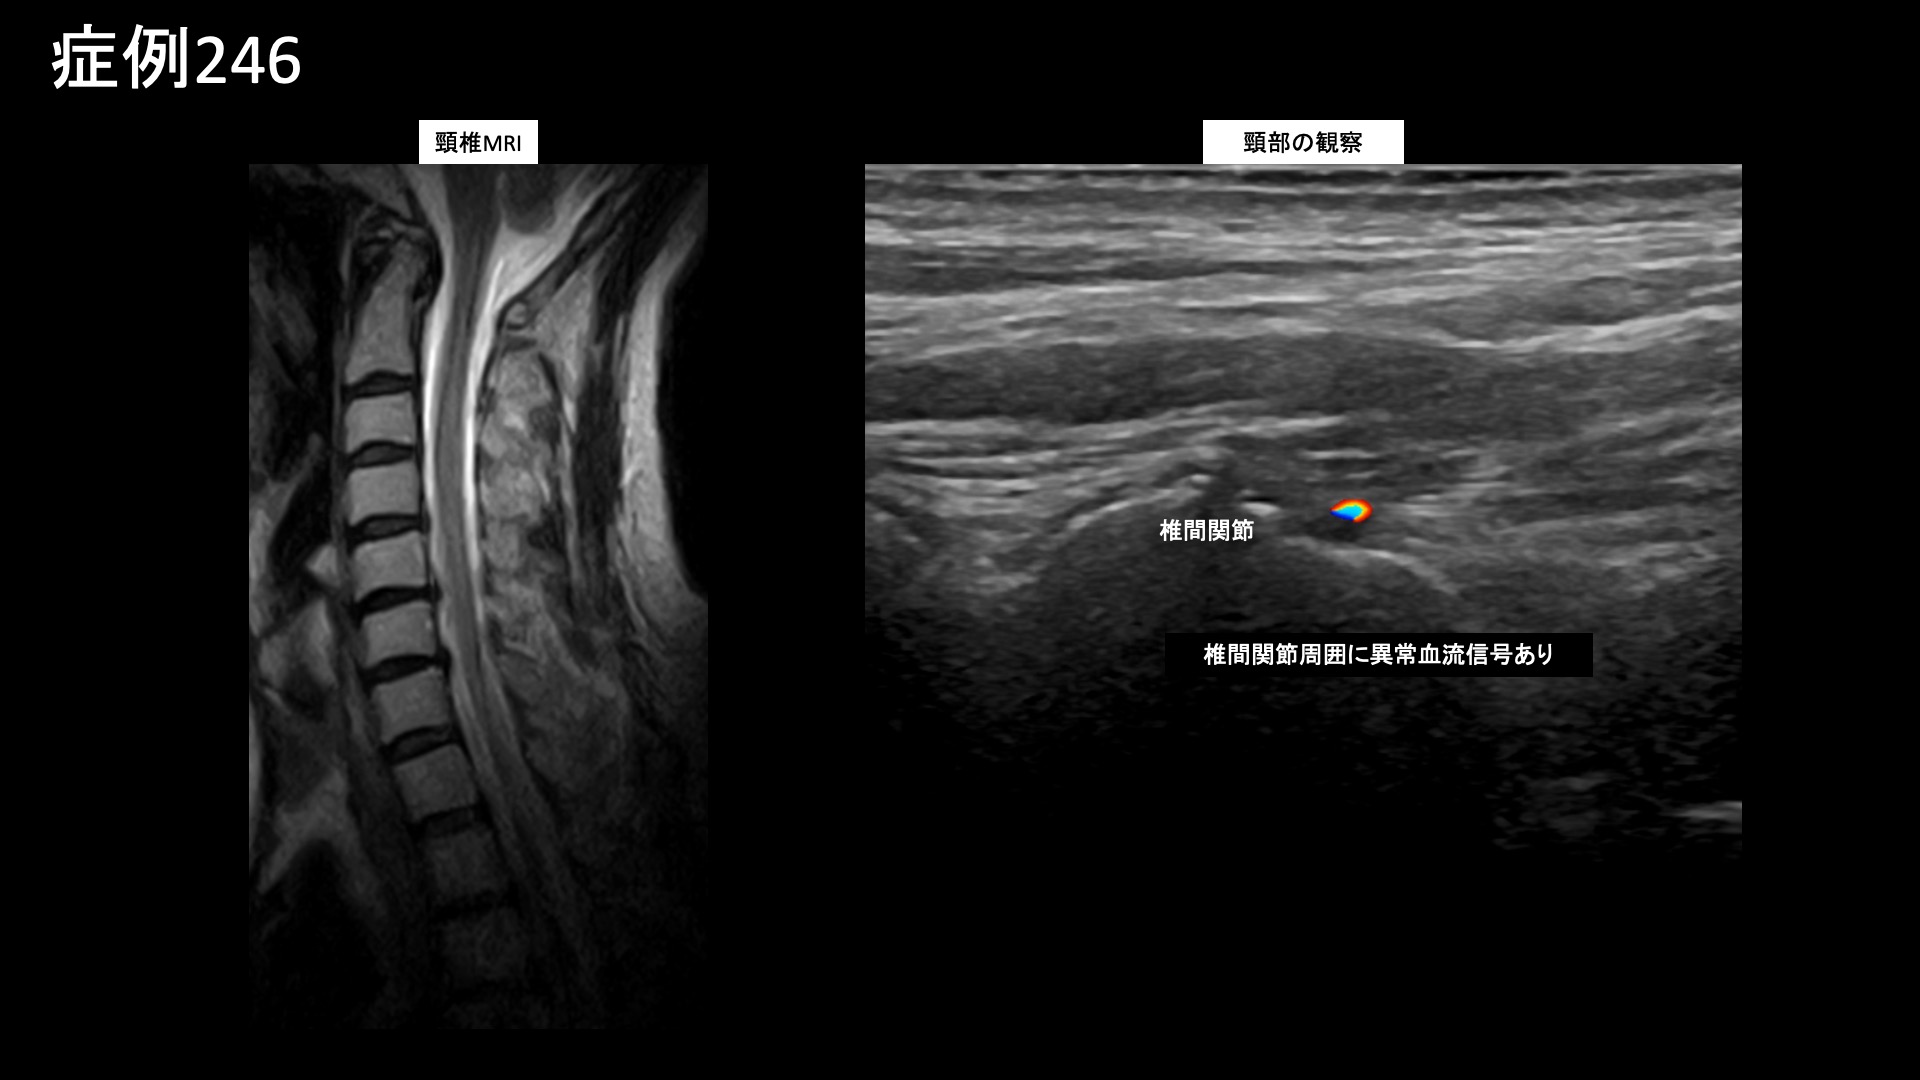

首の可動域は全方向で高度に制限されていました。触診すると、こりの程度は非常に高度であり、圧痛が明瞭に認められました。エコー検査では、僧帽筋および周囲組織の線維化所見を中等度以上認めたほか、頸椎椎間関節周囲においてモヤモヤ血管を反映した異常血流信号を認めました。重症の首肩こりに起因する筋緊張性頭痛として矛盾しませんでした。それだけでなく、顔こり、顎関節症も合併していました。治療適応と判断し、モヤモヤ血管(病的新生血管)に対する運動器カテーテル治療(微細動脈塞栓術)を受けていただきました。尚、本症例の場合は重症度が高い状態でしたので、複数回の治療が必要になる可能性についても事前にご説明しました。